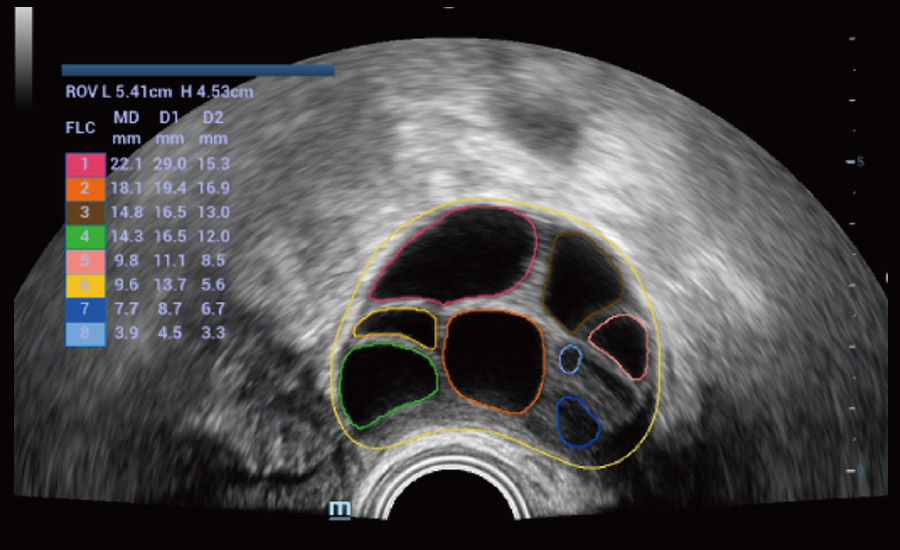

UMA (angiografia ultramicroscĆ³pica)

A tecnologia inovadora elimina as limita??es das tradicionais imagens com Doppler. Com resolu??o espacial e sensibilidade de fluxo ultra-altas, permite a detec??o de perfus?es de fluxos muito sutis e lentos, ampliando assim a aplica??o clĆnica da avalia??o qualitativa e quantitativa do ultrassom no cĆ©rebro fetal, rins, placentas, endomĆ©trios, ovĆ”rios etc.

Informa??es abrangentes adaptadas aos cenƔrios

Por meio da combina??o de algoritmos avan?ados e do conhecimento especĆfico da regi?o, a inovadora solu??o Smart Scene permite a identifica??o automĆ”tica das caracterĆsticas do tecido e fornece diagnĆ³stico especĆfico dos Ć³rg?os com informa??es completas. Com base na identifica??o automĆ”tica de cenĆ”rios, a solu??o realiza n?o apenas a varredura 2D inteligente com configura??es e medidas automĆ”ticas, mas tambĆ©m oferece informa??es 3D abrangentes em todas as etapas, desde a otimiza??o de imagens volumĆ©tricas atĆ© a difĆcil obten??o de planos 2D, e a quantifica??o durante todo o procedimento. Ele ajuda a reduzir em grande parte a dependĆŖncia de habilidades clĆnicas, ao mesmo tempo que aumenta a precis?o, a confian?a e a eficiĆŖncia no diagnĆ³stico.

Fertilidade